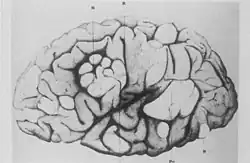

A side profile sketch of a brain, with parts indicated by a letter code. The normal convolutions of the brain are distorted in these areas, forming lumps or thickened folds.

Cerebral tuberous sclerosis showing sclerotic, hypertrophic circumvolutions.

Bourneville and Édouard Brissaud examined a four-year-old boy at La Bicêtre. As before, this patient had cortical tubers, epilepsy and learning difficulties. In addition he had a heart murmur and, on post-mortem examination, had tiny hard tumours in the ventricle walls in the brain (subependymal nodules) and small tumours in the kidneys (angiomyolipomas).[16]